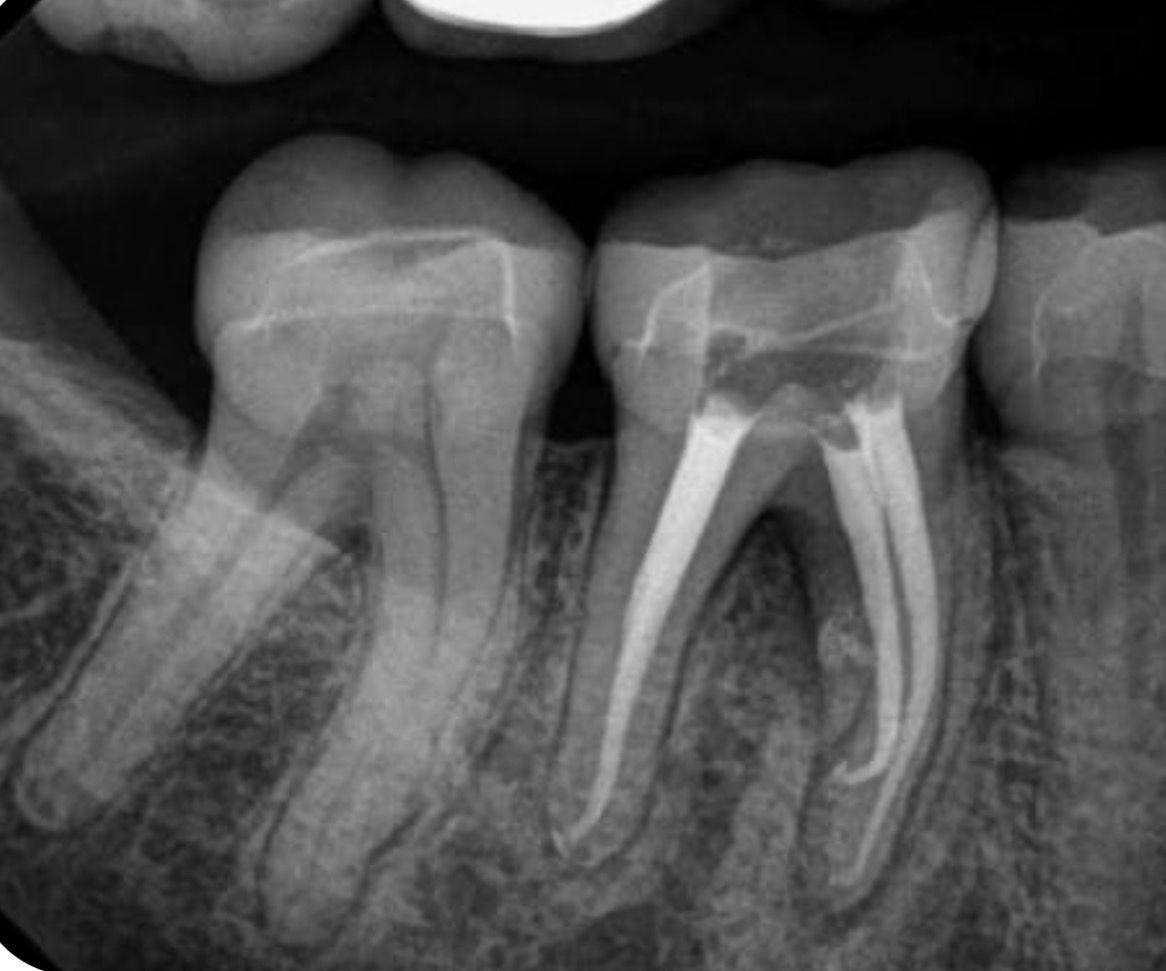

1. Muayene ve Teşhis: Röntgen çekilerek dişin durumu değerlendirilir.

3. Pulpanın Temizlenmesi: Dişin içindeki enfekte veya hasarlı pulpa çıkarılır.

4. Kök Kanallarının Şekillendirilmesi: Kök kanalları özel aletlerle temizlenir ve şekillendirilir.

5. Doldurma ve Restorasyon: Kanallar biyouyumlu bir malzeme ile doldurulur ve genellikle dişin üzerine dolgu, inlay veya kron yapılır.